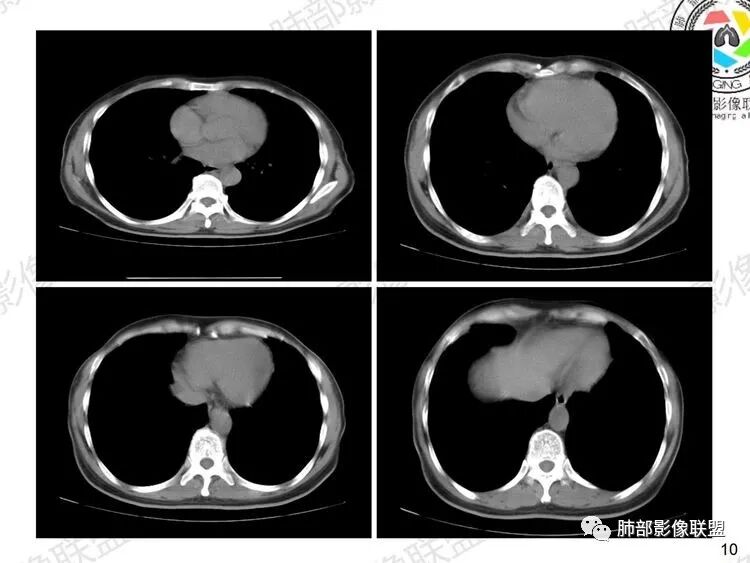

男性病人呼吸困难4个多月,既往有慢支肺气肿,影像学表现为两肺弥漫性的渗出性的改变,马赛克表现,肺动脉主干明显增粗,肺动脉高压的表现。注意排除心源性的肺水肿,肺泡炎、肺出血;感染性病变:过敏性肺炎?卡肺?

①肺水肿:肺间质水肿常有小叶间隔增厚、重力分布趋势。肺泡水肿密度偏高,浑浊一片,肺血管影模糊,且常可找到水肿原发病因(如左心回流障碍、肾功能不全等等)。

(重力趋势是指因液体重力原因导致沿前后方向密度逐次增高)

肺水肿典型的重力趋势:注意小叶间隔的阻挡